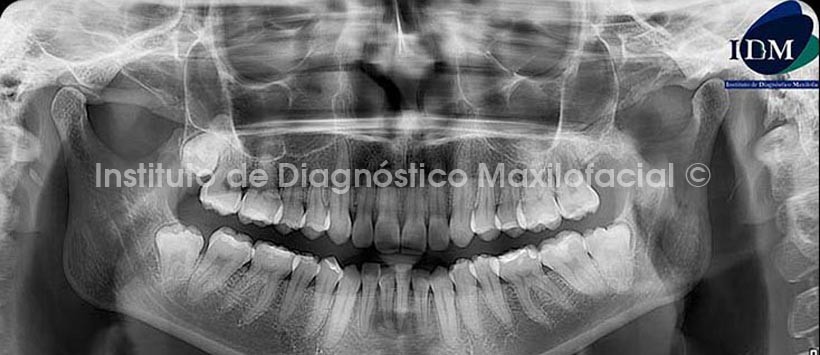

A la evaluación de la radiografía panorámica se observa una lesión de caries oclusal amplia en la pieza 27, además de una radiolucidez difusa a nivel radicular de la misma (Fig 1).